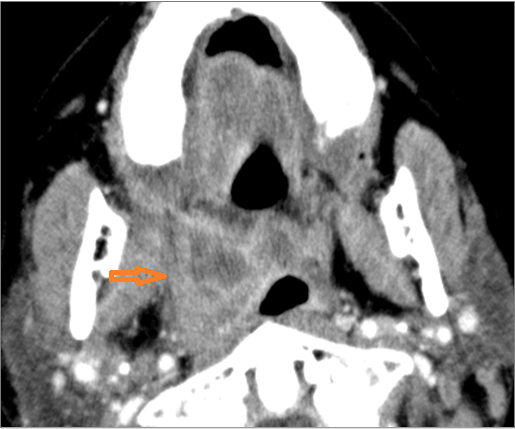

1-year old with fever, difficulties feeding and possible retropharyngeal abscess.Exam

Contrast-enhanced CT of the maxillofacial region and neck and related anatomy with images obtained in the balanced or venous vascular phase to ensure optimal visualization of both arterial and venous structures as well as possible reactive changes around infected collections. 0.5-3.0 mm thick sections were obtained in the axial plane and reformatted 3D and/or in the coronal and sagittal planes and viewed inter actively in 3 dimensions at the computer work station.